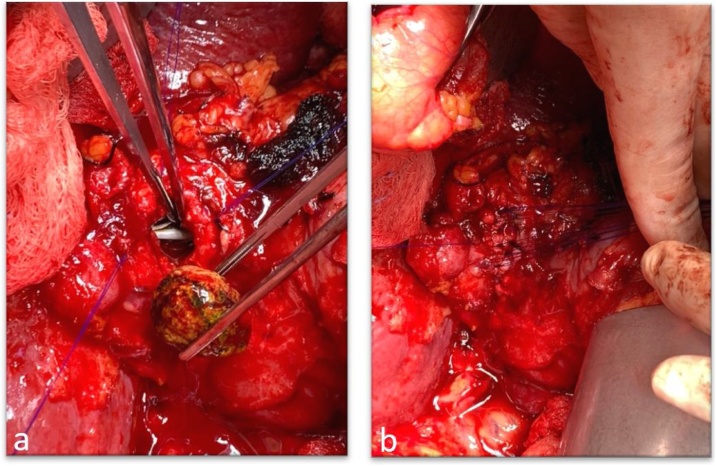

The patient underwent a diagnostic ERCP and was found to have multiple stones in the hepatic ducts as well as a large stone eroding through the wall of the upper third of the common hepatic duct concerning for Csendes type IV Mirizzi syndrome (Fig. 3); stent was placed in the CBD. Following complete preoprative planning, the patient underwent an exploratory laparotomy, bile duct exploration with a choledochotomy and removal of a large biliary stone. The stent was visible in the lumen of the bile duct (Fig. 4a) and the remainder of the gallbladder neck was used to primarily repair the defect using interrupted sutures (Fig. 4b).

Our patient had biopsies negative for malignancy. Due to the large defect of the common biliary duct, reconstruction of the duct was made using remnant walls of the gallbladder neck using interrupted stiches, leaving the stent in place (Fig. 4).